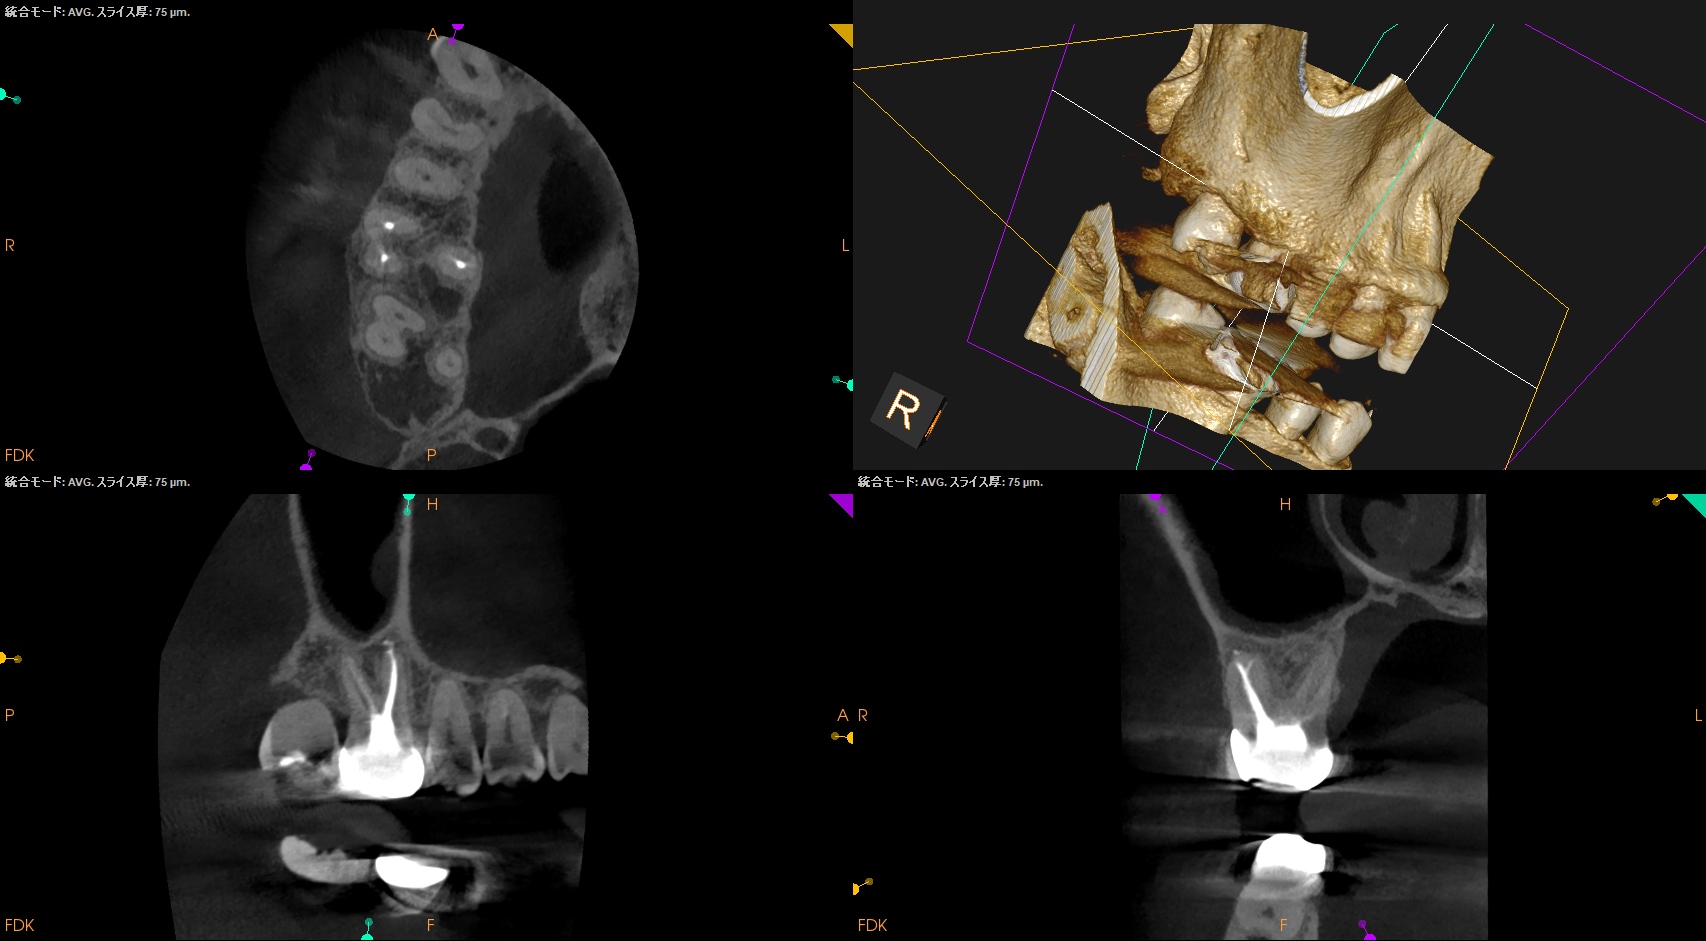

PA, CBCTも撮影した。

B

初診時と比較した。

はみ出たBC sealerが消失して歯槽骨と置き換わっている

という臨床的事実だ。

このケースではみ出たBC sealerが歯槽骨に置き換わったのか?私にはわからない。

が、根尖病変が治癒し歯槽骨に置き換わったのは紛れもない事実だ。